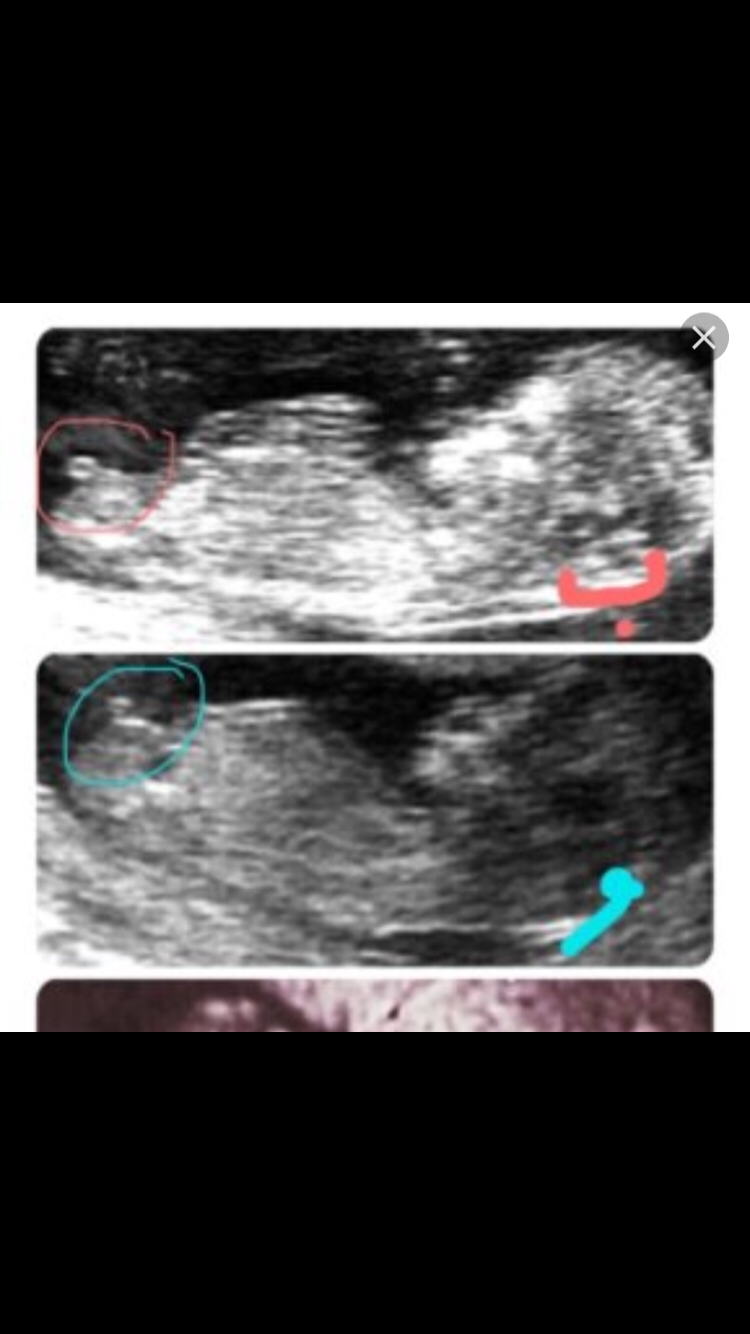

لاحظوا بالصورة الاولى البروز افقي وواضح انه بنت الصورة الثانية البروز الى اعلى وواضح انه ولد سبحان الله

بنات الي عندها سونار تشوف النظريه هذه تنطبق عليها ولالا نظرية الناب طبعا الاجانب يؤكدون عليها وكذا هنا حسابات حمل وذا يؤكدونها ياليت نشوف صدقت معاكم ولالا لاحظوا بالصورة الاولى البروز افقي وواضح انه بنت الصورة الثانية البروز الى اعلى وواضح انه ولد سبحان الله